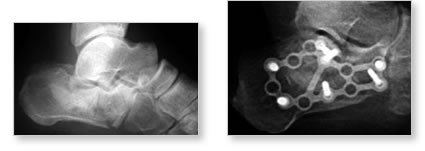

Surgical treatment

If the bones have shifted out of place (a displaced fracture), you will most likely need surgery. A metal plate and small screws are used to hold the bones in place. A bone graft may be used to aid in the healing of the fractures. The incision will be bandaged and a splint applied until it is healed. Then, you’ll get a removable splint so that you can begin exercising the joint. You won’t be able to put any weight on your foot for approximately 10 weeks after surgery. When you begin walking, you may need to use a cane and wear a special boot. It may take up to a year for the injury to heal completely. Depending on the type of job you have, you may not be able to return to the same type of work. Because of the amount of force needed to break the heel bone initially, even if your fracture heals properly, your foot may never be the same as it was before the injury. You may continue to experience stiffness and you may need to wear a heel pad, lift, or cup as well as special shoes with extra depth in the toe compartment.